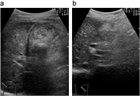

1. 急性胆嚢炎の原因の90~95%は胆嚢結石であり、結石の嵌頓による胆嚢管閉塞と胆嚢内胆汁うっ滞に引き続き、胆嚢粘膜障害が起こり、炎症性メディエーターの活性化が引き起こされる。